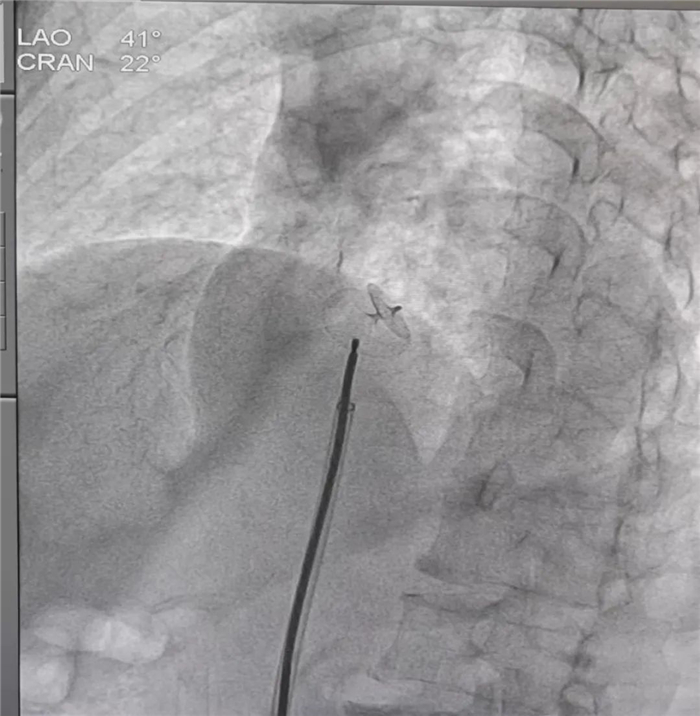

朱永彪主任手術(shù)中

據(jù)悉,患者羅女士(化名)來自拉薩市,今年61歲,既往有反復(fù)頭暈、心慌等不適癥狀,7月6日到我院心血管內(nèi)科就診。經(jīng)右心造影檢查明確患者為卵圓孔未閉,經(jīng)心血管內(nèi)科全科室研究討論后,決定為該患者進(jìn)行卵圓孔未閉介入封堵術(shù)。13日下午,在心內(nèi)科主任朱永彪的指導(dǎo)下,我院心血管內(nèi)科通力合作,用介入封堵術(shù)取代外科手術(shù),通過一根導(dǎo)管,經(jīng)右股靜脈途徑將封堵器沿輸送鞘置入并成功封堵卵圓孔,術(shù)中多角度顯示封堵器形態(tài)良好。

手術(shù)成功